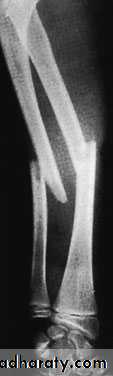

Mechanism of injury and pathologyFractures of the shafts of both forearm bones occur quite commonly. A twisting force (usually a fall on the hand) produces a spiral fracture with the bones broken at different levels. An angulating force causes a transverse fracture of both bones at the same level. A direct blow causes a transverse fracture of just one bone, usually the ulna.

Both bones are broken, either transversely and at the same level or obliquely with the radial fracture usually at a higher level. In children, the fracture is often incomplete (greenstick) and only angulated.X-RAY